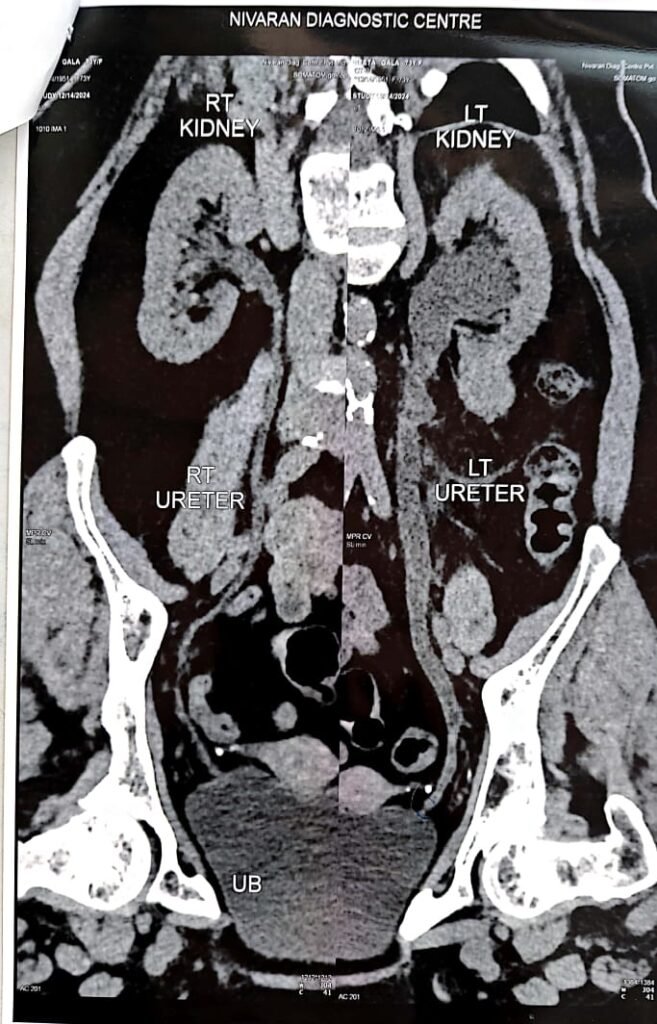

We combine Ayurvedic treatment with modern diagnostics: